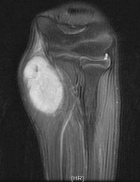

15 year old boy with left elbow mass for five years that has increased in size over the last few months as well as becoming more painful